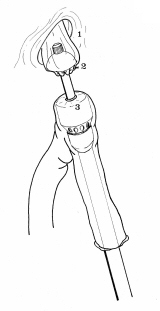

器械吻合器テクニックあれこれ

あのころ、実用化されたばかりの自動吻合器の使用上の「コツ」シリーズ。